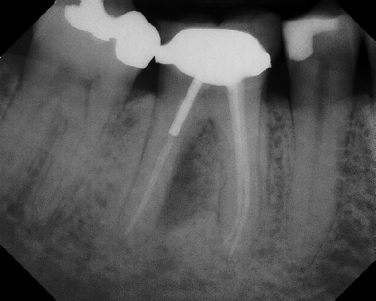

COMPLICATED ANATOMY LARGE LESIONS CALCIFIED CANALS PERFORATION / RESORPTION SEPARATED INSTRUMENTS SURGICAL CASES RETREATMENT / pOST REMOVAL OPEN APICES ACCESS THRU CROWNS Root Canal Case Portfolio